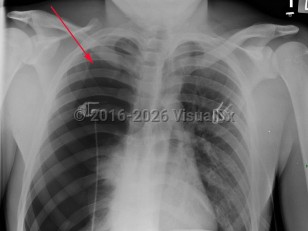

Pneumothorax

Spontaneous pneumothoraxSpontaneous pneumothorax

Tension pneumothorax